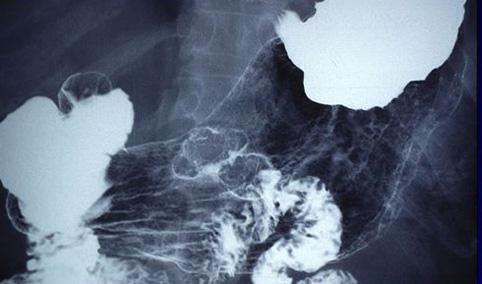

clasificación del pacienteTumor Epitelial Maligno/Adenocarcinoma

parte(separada por órganos)estómago(región)/cuerpo

método de exámenRayos X

clasificación ectoscópica de tumoresTipo 0(tipo superficial)/Tipo I(I)

diámetro mayor del tumor20 - 24

grado de penetraciónm

múltiples tumores(en un mismo órgano)presente(simultáneo)